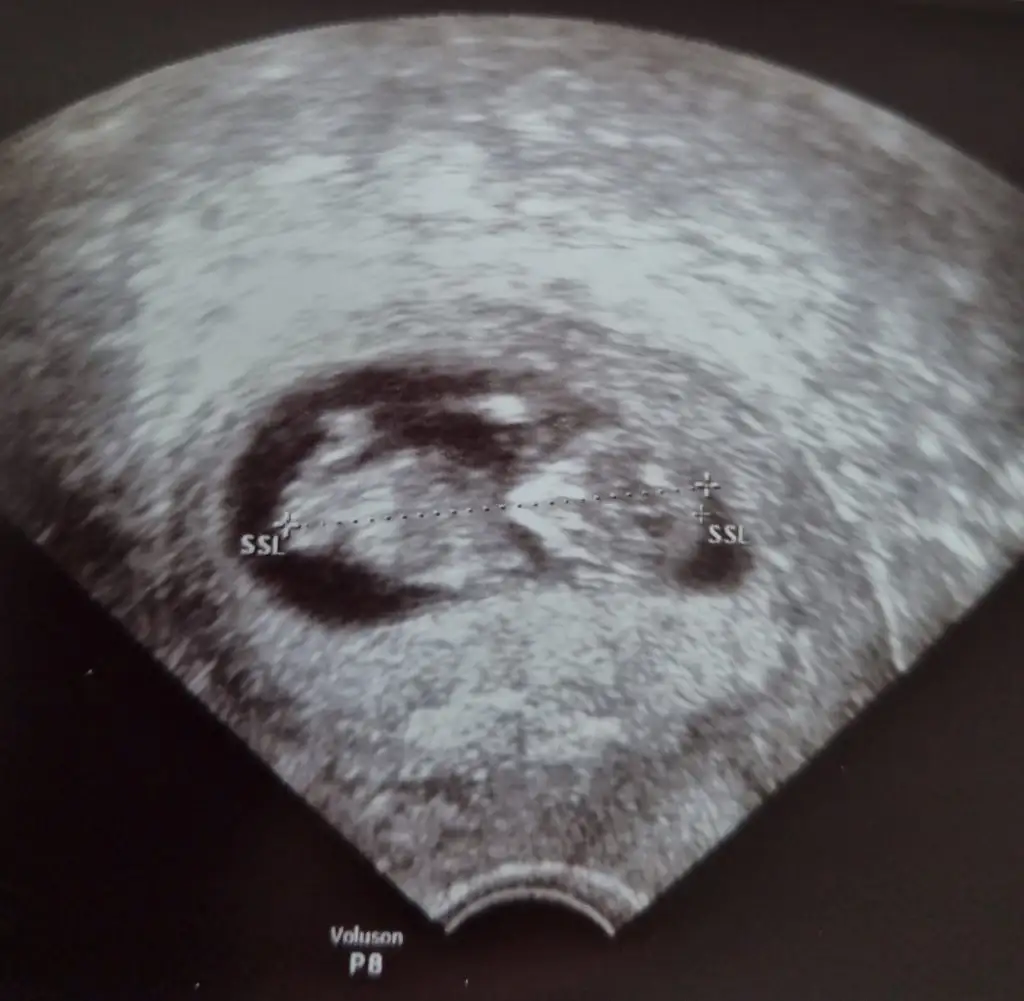

Net değil USG başka USG varsa paylaşın sanki kız gibi amin olamadım12+5 acaba tahminde bulunabilir misinizEki Görüntüle 2785401

Ya başka ultrason yok ama 9+5 bir ultrasonum var. Doktor şimdilik erkek gibi dedi ama bilmiyorumNet değil USG başka USG varsa paylaşın sanki kız gibi amin olamadım![]()

Emin olamadım zaten belki erkektir olursa USG paylaşınYa başka ultrason yok ama 9+5 bir ultrasonum var. Doktor şimdilik erkek gibi dedi ama bilmiyorum![]()